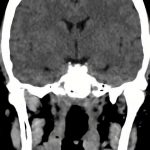

下垂体腺腫

断層撮影

手術前1

手術後

No.’14_161 手術前1

No.’14_161 手術後